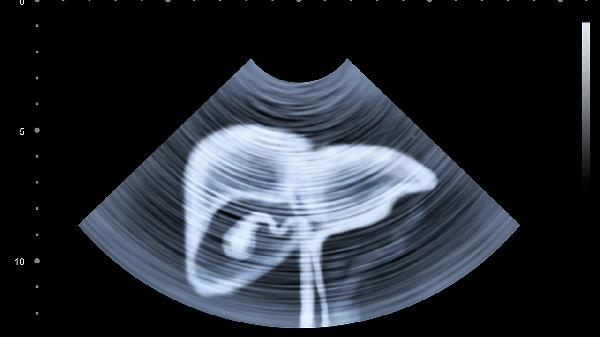

日常需保持规律作息,避免久坐,每日进行30分钟适度运动如散步、瑜伽等。饮食上选择易消化的食物,少量多餐,限制辛辣刺激食物摄入。若症状持续不缓解或加重,应及时到消化内科或妇科就诊,完善便常规、尿常规、超声等检查。注意记录症状变化及诱因,便于医生评估病情。